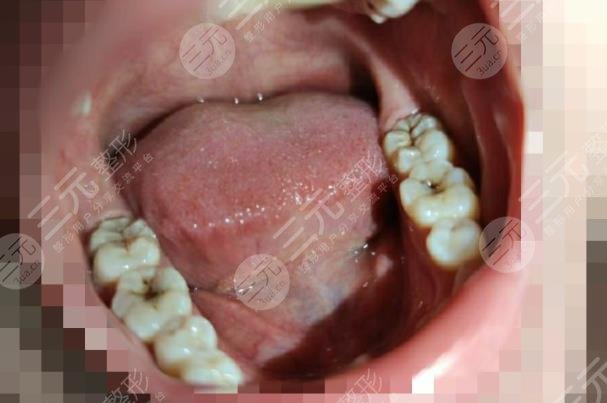

目前如果想要补一颗牙齿,大概的价格在200元左右起,当然具体的价格并不恒定,与个人的治疗情况以及方案的选择有关。补牙是较简单,同时也是较基础的一项操作,通过材料的填充GET填补漏洞的果。如果选择质量较好,比较理想的填补材料,维持的时间会更加具有一些比较耐磨耐腐蚀。如果选择的材料坚固性较差,有可能出现进一步的损伤。另外为了大家能够了解目前市面上的口腔项目的价格,下面我们给大家整理了一个价目表。